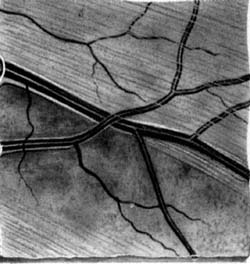

Je tvořena axony gangliových buněk pokrytých astrocyty, probíhajících v kanálcích z výběžků Mullerových buněk ve svazečcích o průměru 20 um. Svazečky jsou morfologickým podkladem jemného žíhání. Světlé proužky mezi tmavými mezerami jsou výběžky Mullerových buněk, ve kterých probíhají nervová vlákna. Temporálně i nasálně je žíhání jemné a každý proužek je tvořen jedním svazečkem vláken. V horním i dolním temporálním kvadrantu je jsou proužky silnější a tím i lépe viditelné, každý proužek má několik svazečků (svazečky jsou v několika vrstvách).

Lokalizovaný výpadek nervových vláken byl popsán poprvé teprve roku 1973 Hoytem. Je vějířovitého tvaru, připomínající ocas komety. Vyskytuje se u 20% glaukomů, není však pro glaukom specifický (drůzy, chorioretinální jizvy, dlouho trvající edém disku, pozánětlivá atrofie). Není u zdravých očí.

Při progresi glaukomu nejprve bývají poškozeny gangliové buňky v blízkosti temporálního švu sítnice. Jejich axony probíhají v hlubší vrstvě nervových vláken a do zrakového nervu pronikají v jeho periferii. Protože vzniklý defekt je překryt dalšími povrchnějšími vrstvami, výpadek není při pozorování sítnice zřetelný. Až po ztrátě poloviny vrstvy nervových vláken se defekt stává zřetelným oftalmoskopicky.

Difusní výpadek nervových vláken vzniká při více méně rovnoměrném úbytku gangliových buněk a jejich vláken po celé sítnici. Zrakový nerv mívá koncentrickou exkavaci a plocha neuroretinálního lemu bývá úzká. Klinicky se tento výpadek nejlépe pozná při pohledu na cévy, které jsou kryty jen vnitřní limitující membránou a při pohledu přímým oftalmoskopem mají na první pohled nezvykle ostré hranice, jakoby vystupovaly nad povrch sítnice.